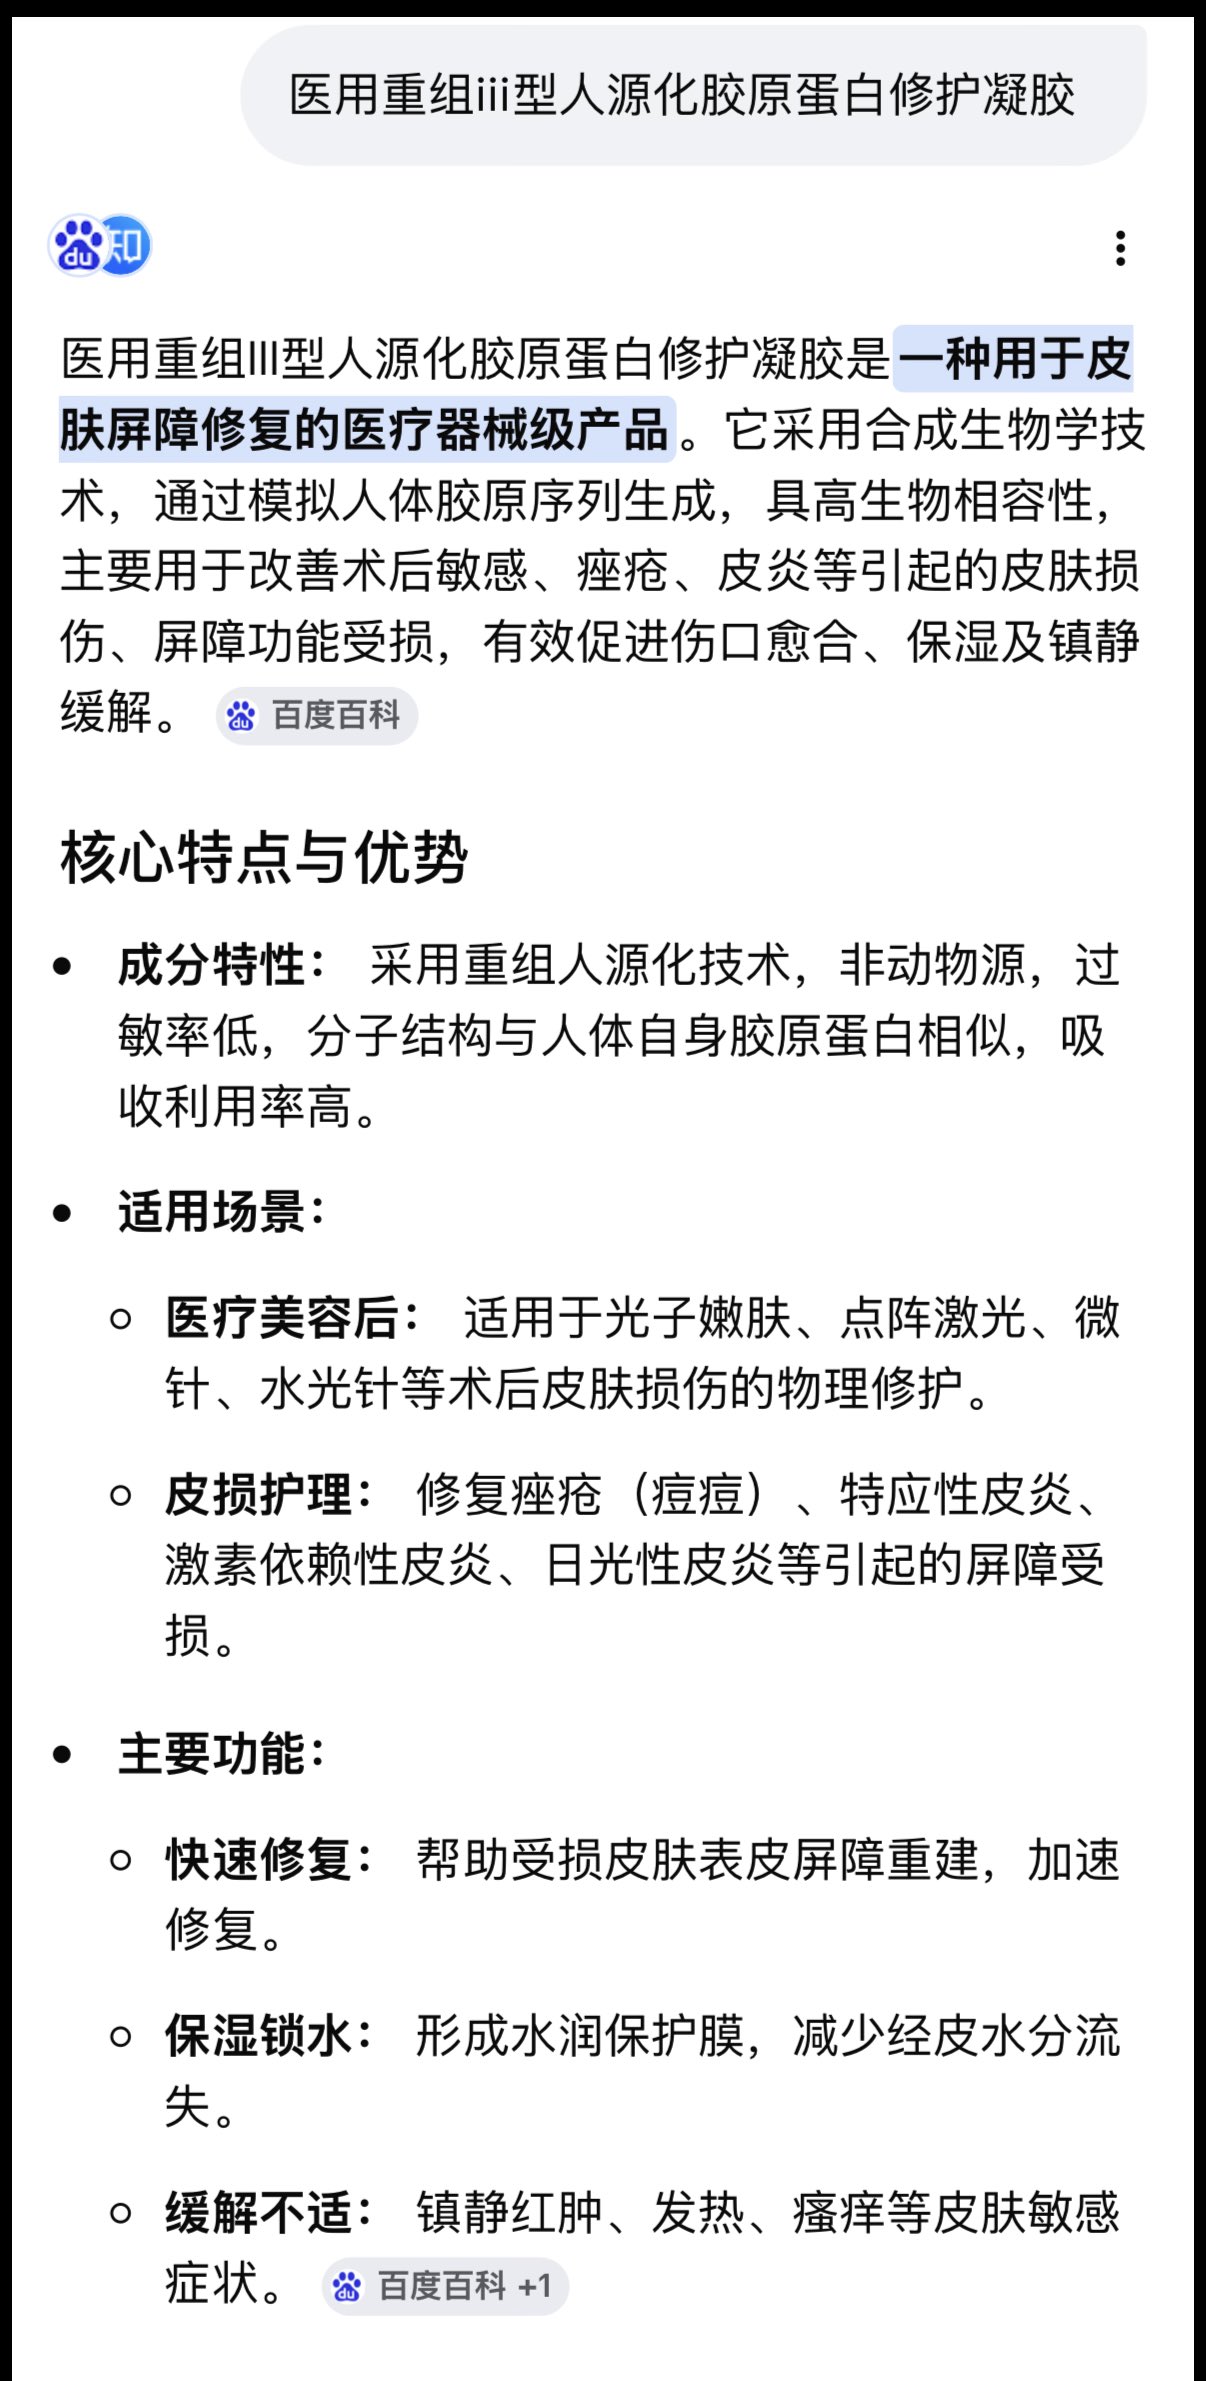

2024-08-14 11:34:53 UTC

甚至在第二天有余晖的感觉,虽然发生了很多破事但没怎么影响心情*抗焦虑&镇静

运动协调性稍差,表现为走路和站立时平衡不好

此剂量下对睡眠的改善作用,增加了慢波睡眠且没有影响rem,精力恢复+

FDA数据,在临床剂量下(75-600mg)普瑞巴林的依赖性低于bzd,并相比之下它产生的认知和精神运动障碍较轻 https://t.co/TJ7ZOQ7pbC